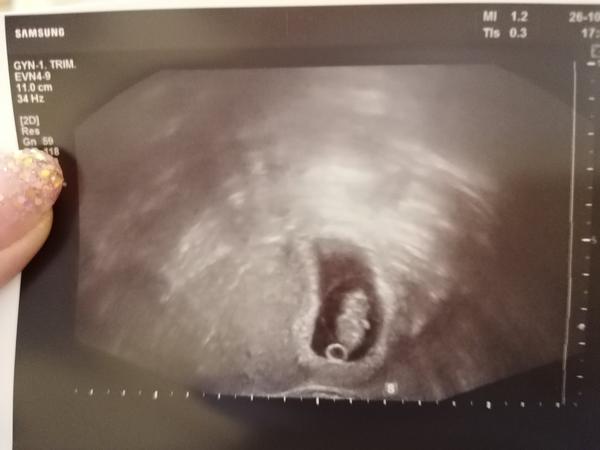

Ultrazvuk. Vše ok?

Ahoj všem, jsem tu nová. Čtu tu zprávy často od vás. Mám na Vas otázku. Jsem teď cca 9 týden, minulý týden jsem byla u gynekologa, nechala jsem si udělat první fotecku. Ale podle hlavičky se mě zdá tam něco špatně. Vím že to je brzo, prosím řekněte mě, jak se vám jeví ta fotecka. Když na to furt koukám, říkám jestli to je v pohodě nebo ne. Děkuji

Úplně normální utz

Jinak to, co popisuješ jako cystu podle mě vůbec žádná cysta není. Nejsem gynekolog ani z žádného blízkého oboru, ale mám dojem, že jsem něco takového měla u všech tehotenstvi a myslím, že dr mluvil o žloutkovém váčku. Ale o časté nikdy. A kdyby to cysta měla být určitě by ti to dr řekl.

@werumka je tam cysta, doktor mě řekl, že to je cysta. Zjistila jsem ji na preventivní kontrole, že nemám teď ovulaci, za 3 týdny jsem šla na kontrolu po lécích na cystu, aby vymizela a řekl mě že jsem v 5 týdnu. Ale říkal že se z cysty asi stal ten váček. Takže teď to už není cysta ale ten váček? A ten je v pořádku? Má tam být?

Vypadá to normálně 👍